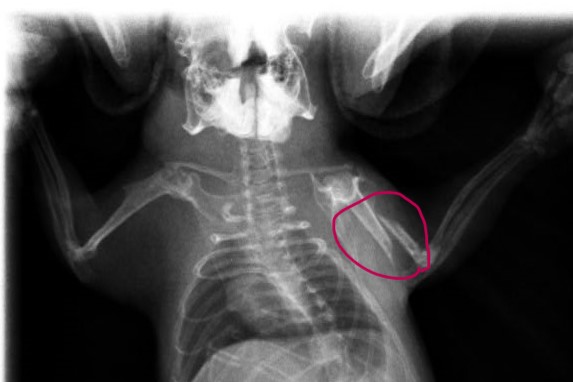

【診断】

骨折すると、足を浮かせて着地を避ける、異常な角度での四肢の保持、動きの低下、痛みを訴えるような行動などが観察されます。視診と触診に加え、レントゲン検査が確定診断に必要です。画像により骨折の位置、ずれの有無、骨片の数や形状、関節への影響などを把握し、治療方針を決定します。